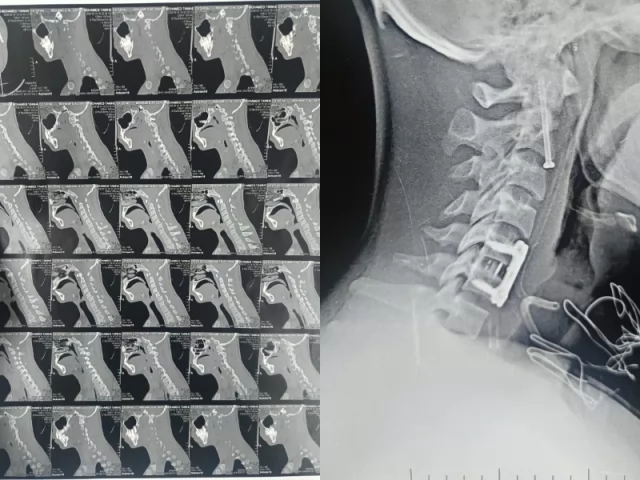

استقبل قسم الاستقبال والطوارئ بالمستشفيات مريضاً إثر سقوطه من علو، وبالفحص الدقيق تبين إصابته بكسر في الفقرة العنقية الثانية، وهو موقع شديد الخطورة لقربه من جذع المخ والحبل الشوكي، كما كشفت الفحوصات والأشعة عن وجود تزحزح فقاري بين الفقرتين الخامسة والسادسة.

أُجريت الجراحة تحت إشراف الأستاذ الدكتور إسلام أبو الفتوح رئيس قسم جراحة المخ والأعصاب، وبمشاركة فريق التخدير بقيادة الأستاذ الدكتور إيهاب سعيد رئيس قسم التخدير، حيث تمكن الفريق الطبي من تثبيت كسر الفقرة العنقية الثانية بدقة عالية، إلى جانب تثبيت التزحزح الفقاري بين الفقرتين الخامسة والسادسة باستخدام شريحة ومسامير وقفص عنقي.

وبفضل الله وبراعة الفريق الطبي، تكللت الجراحة بالنجاح دون حدوث أي مضاعفات، حيث يتمتع المريض حالياً بحالة صحية مستقرة وكامل حركته وعلاماته الحيوية، ويخضع للمتابعة الطبية حتى تمام الشفاء.